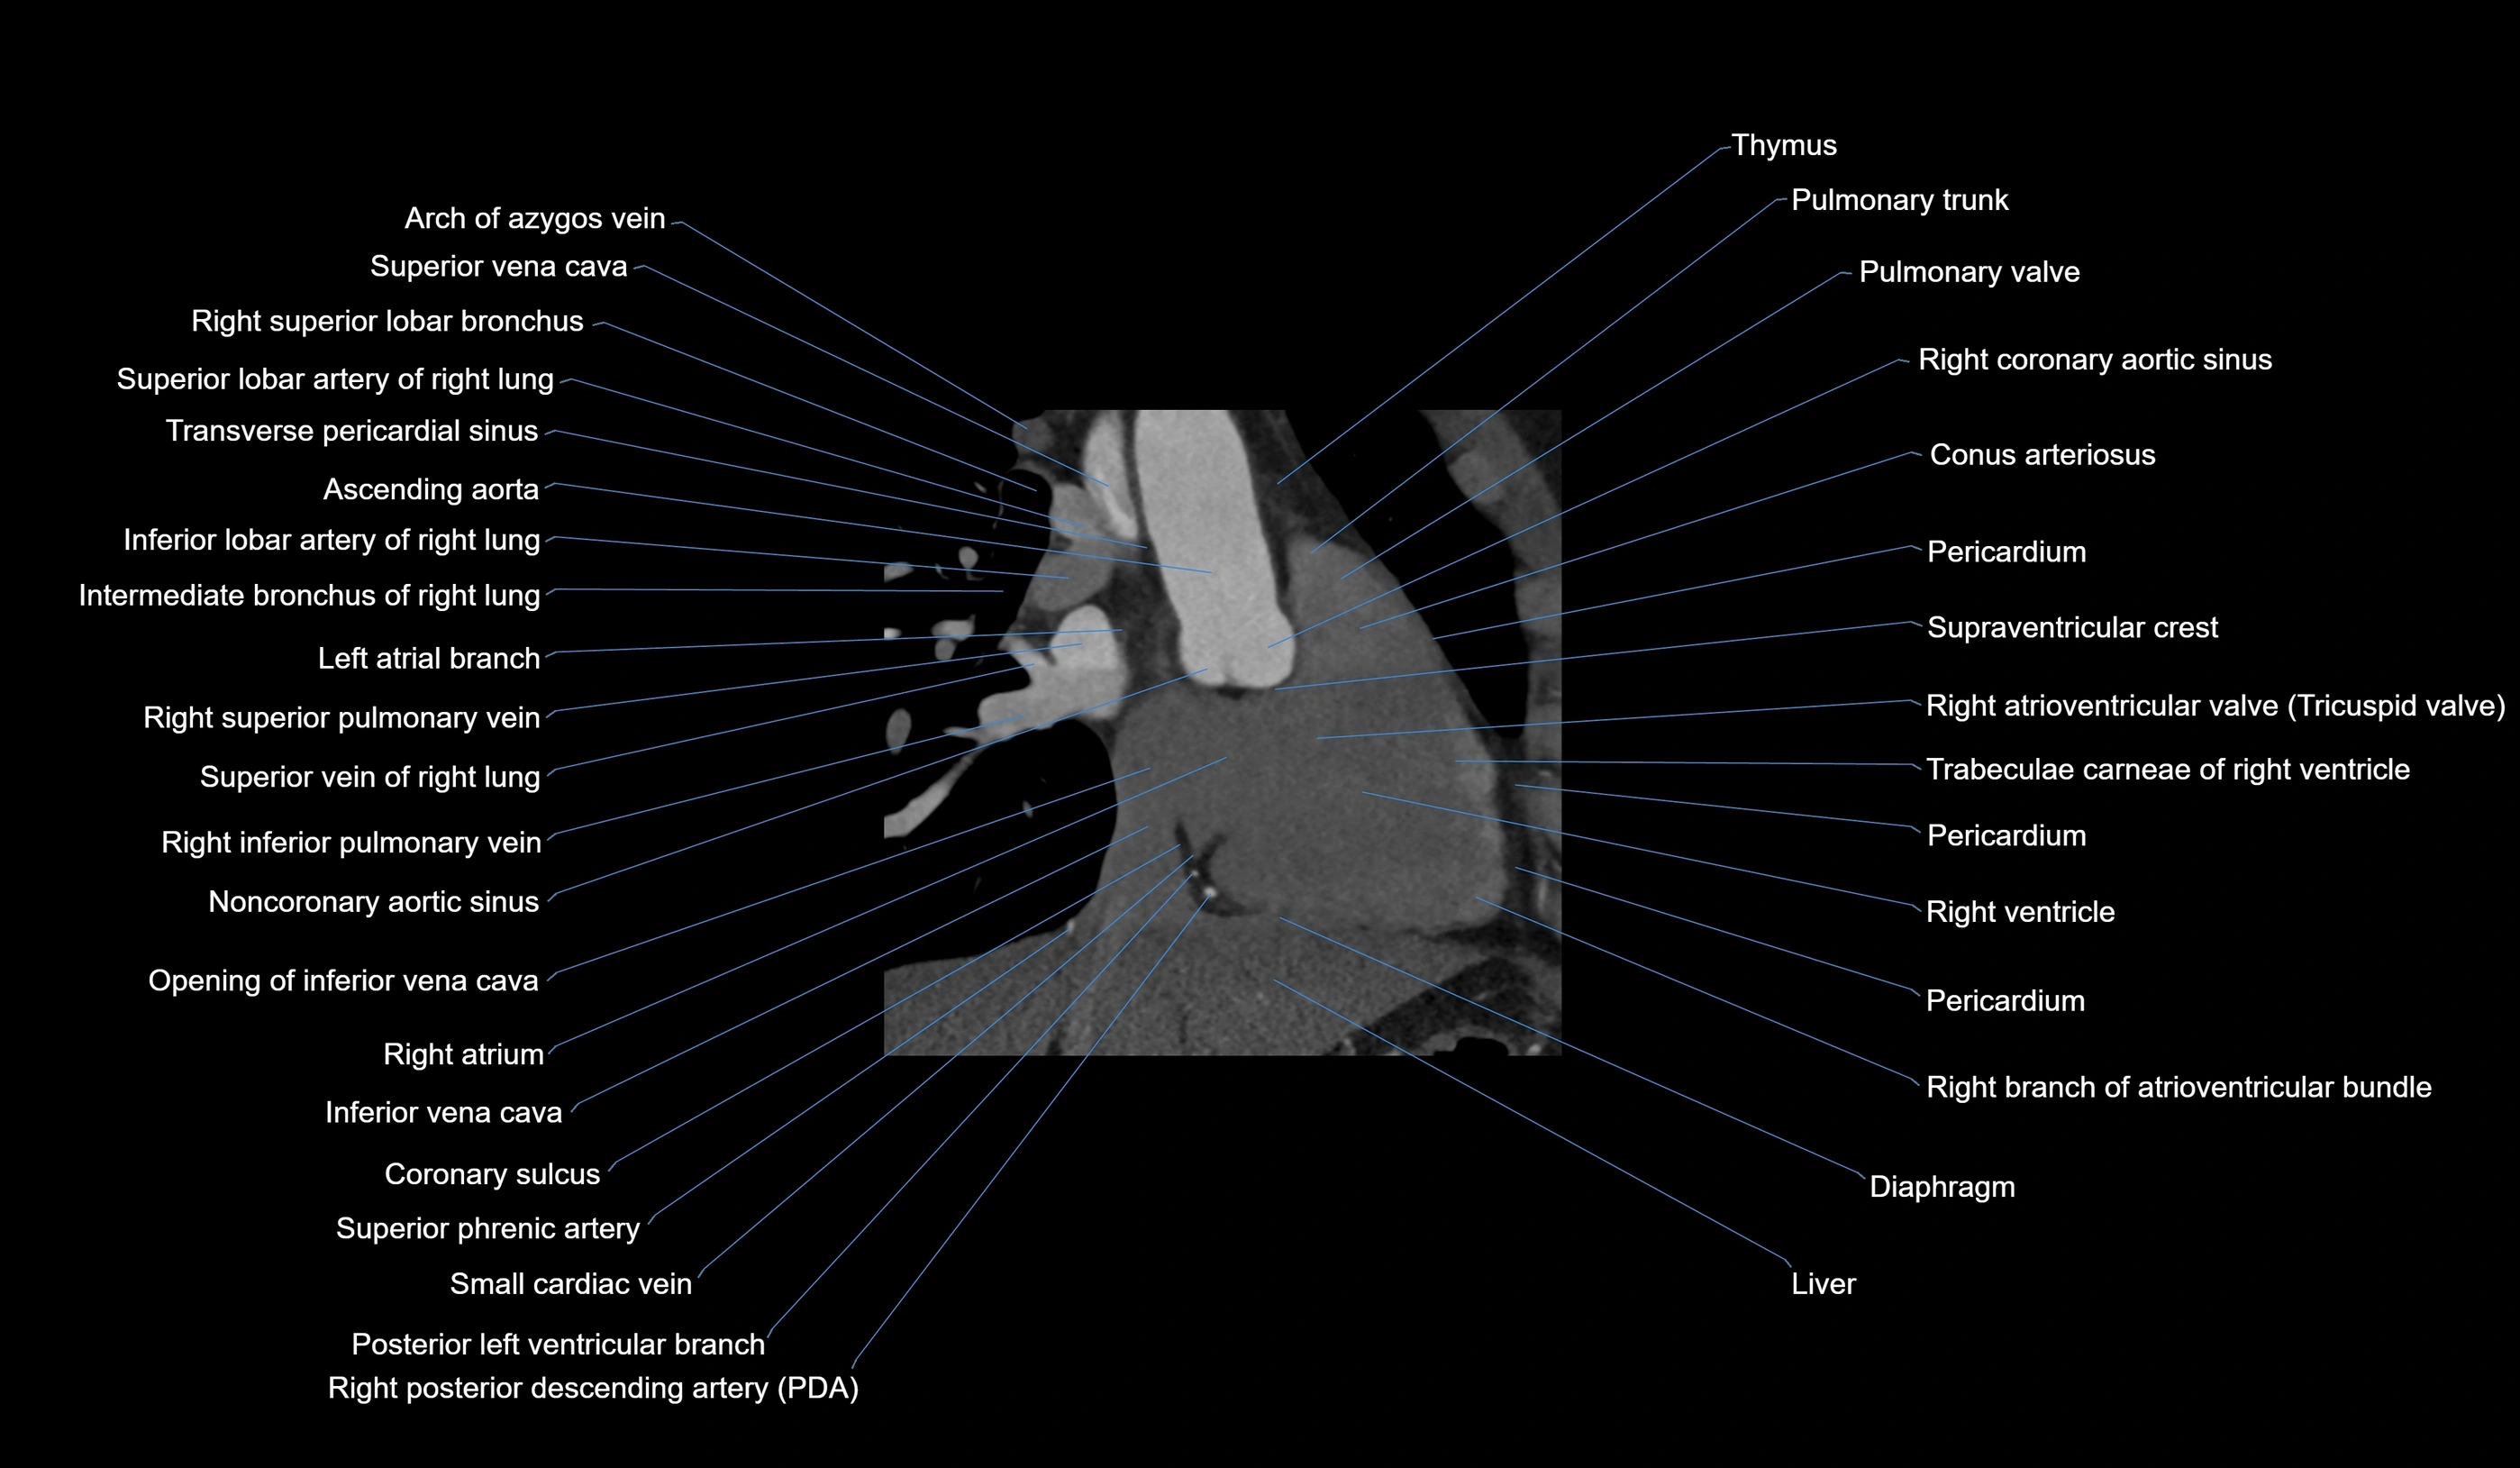

- Ascending aorta

- Azygos vein

- Conus arteriosus

- Diaphragm

- Inferior lobar artery of right lung

- Inferior phrenic artery

- Inferior vena cava

- Pulmonary trunk

- Pulmonary valve

- Right atrioventricular valve (tricuspid valve)

- Right atrium

- Right branch of atrioventricular bundle

- Right coronary aortic sinus

- Right coronary artery (RCA)

- Right inferior pulmonary vein

- Right interlobar artery

- Right intermediate bronchus

- Right posterior descending coronary artery (Right PDA)

- Right superior lobar bronchus

- Right superior pulmonary vein

- Right ventricle

- Small cardiac vein

- Superior vena cava

- Transverse pericardial sinus